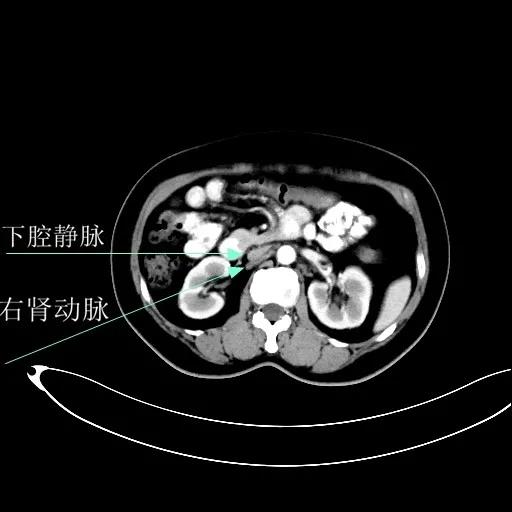

某患者因为“腹痛1周”而入院,外院B超提示子宫上方囊实性肿物,CT提示:左侧附件区占位,并盆腔及腹主动脉旁淋巴结转移。右肾动脉有右肾动脉及异位右肾动脉,其下均有肿大淋巴结。

肾血管总体变异率为35%左右,左侧型发生率为7.5%-23.5%,右侧型发生率为10%-25.3%,双侧型发生率为5.7%。肾动脉一般走行于肾静脉后方。本例异位右肾动脉由腹主动脉发出,经肾静脉前方走行进入右侧肾门,因此称为异位右肾动脉。不论哪个肾动脉分支,均为肾脏相应区域的终末供血动脉,如果发生病变或手术损伤,即可造成相应区域的缺血坏死,因此肾动静脉下淋巴结切除术过程中需警惕异位肾动脉或副肾动脉的存在。

排除禁忌后,在全麻下行“次广泛子宫切除+双附件切除+大网膜切除+阑尾切除术+盆腔淋巴结及腹主动脉旁淋巴结切除术”。术中切除腹主动脉左旁、右旁及后方淋巴结,达左右肾动静脉水平。多个淋巴结呈融合状态,长径约3-5cm。手术由陈亮副主任医师和宋趣清主治医师完成。